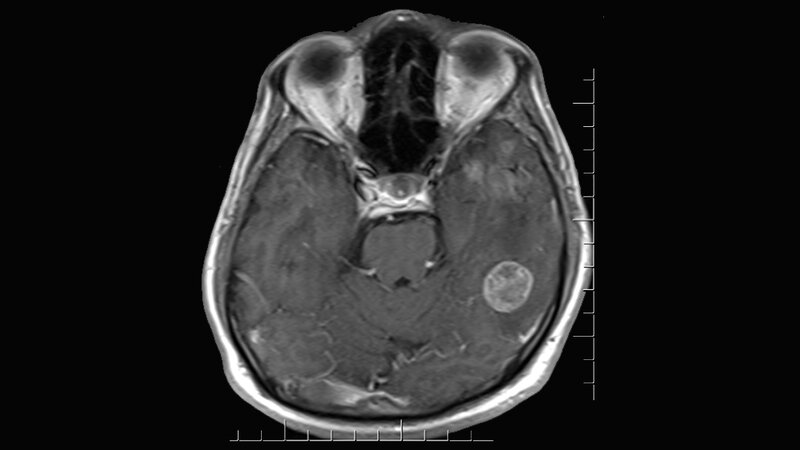

„Viele Patienten schrecken deshalb vor einer Strahlentherapie zurück, obwohl diese den Tumor nachweislich für viele Monate zurückdrängen kann“, erläutert Prof. Combs. Eine schonende Alternative gegenüber der Ganzhirnbestrahlung ist die hochdosierte, lokalisierte Strahlentherapie, wie die stereotaktische Radiotherapie. Bei der Behandlung werden Komplikationen weitestgehend vermieden durch die Behandlung mit einem Spezialgerät, welches eine punktgenaue Bestrahlung ermöglicht. Durch eine präzise, hochauflösende Bildgebung (u.a. Magnetresonanztomographie) wird dieser Punkt vorher bestimmt.

Nach der Entfernung des Tumors kann die Operationshöhle dann bestrahlt werden. „Diese Behandlung ist dann ganz fokussiert auf die ehemalige Metastasenregion. Wir sprechen von einer fokalen Bestrahlung, die in nur wenigen Behandlungstagen durchgeführt wird, in vielen Fällen sogar ohne einen Krankenhausaufenthalt“, erläutert Professor Combs. Diese Art der Bestrahlung sei besonders schonend für die restlichen Regionen des Gehirns, wodurch kognitive Störungen weitestgehend vermieden werden können, so Combs. Dabei bezieht sie sich auf zwei aktuelle Studien.